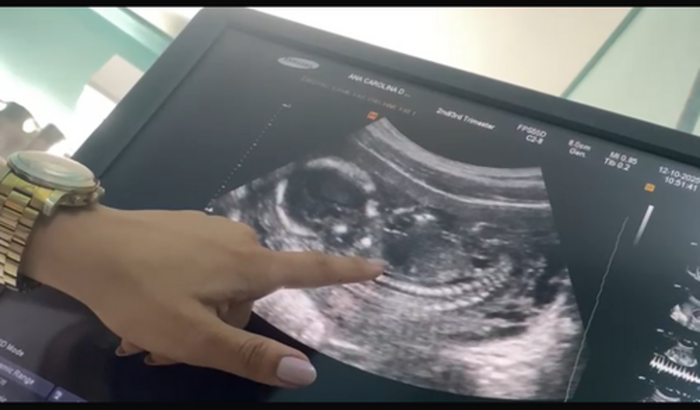

Estou grávida e fui diagnosticada com baixo líquido amniótico, mas graças a Deus meu bebê continua forte e lutando comigo todos os dias.

Descobri um médico especialista em saúde fetal , pra conseguir entender melhor o meu caso, e oq realmente está acontecendo , porém o custo é um pouco alto , e infelizmente no Sus estou na fila de espera e aguardando vaga , geralmente demora uns 3 meses.